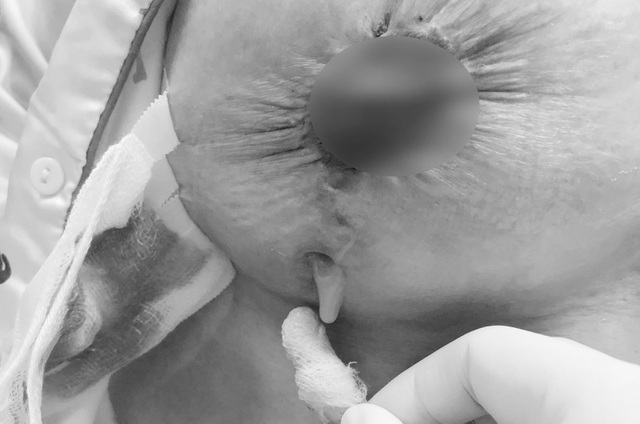

Bệnh nhân là chị T.T.N. (43 tuổi, ngụ tại Kiên Giang). Chị N. đến một bệnh viện thẩm mỹ ở TP Hồ Chí Minh trong tình trạng hai bên ngực đau nhức co thắt, cơn đau lan khắp bả vai. Qua thăm khám, bác sĩ phát hiện ngực bên phải của bệnh nhân thủng lỗ sâu, vùng da rách toạc với lỗ thủng to với diện tích 5cm2. Chỉ cần chạm nhẹ là dịch mủ vàng hôi trào ra ngoài với lượng lớn.

Nữ bệnh nhân nhập viện trong tình trạng bầu ngực trào mủ, bốc mùi hôi thối

Mủ dịch liên tục tuôn trào, miệng vết mổ không thể lành thương trở thành hố giếng sâu trên ngực

Qua thăm khám lâm sàng và chẩn đoán hình ảnh, TS.BS Nguyễn Phan Tú Dung nhận định đây là một trường hợp nhiễm trùng ngực lan rộng nghiêm trọng, cần phải mổ khẩn cấp. Khi thực hiện cuộc phẫu thuật, bác sĩ phát hiện ngực bệnh nhân không ngừng chảy dịch vàng lẫn máu mủ và thông hẳn vào bên trong khoang ngực khiến ekip gặp nhiều khó khăn trong quá trình bóc tách. Ê kíp phẫu thuật ngỡ ngàng khi phát hiện miếng băng gạc "bỏ quên" trong khoang ngực của bệnh nhân.

Miếng gạc bị bỏ quên trong cuộc phẫu thuật tại Spa là nguyên nhân khiến người bệnh bị nhiễm trùng

Đây chính là nguyên nhân gây nhiễm trùng ngực và tích tụ ổ áp xe dịch mủ khổng lồ trong ngực bệnh nhân. Suốt 3 giờ thực hiện cuộc mổ, các bác sĩ đã nhanh chóng tháo túi ngực cũ, kiểm tra kỹ lưỡng khoang ngực để chắc chắn không còn bất kỳ dị vật nào sót lại, đồng thời bơm rửa, cắt lọc mô hoại tử, khâu tạo hình khép lỗ thủng trên ngực phải cho bệnh nhân để vừa đảm bảo an toàn và thẩm mỹ.

Bác sĩ Tú Dung bức xúc: "Chưa bao giờ tôi tiếp nhận một trường hợp biến chứng như thế này. Đây không chỉ là vấn đề về kiến thức chuyên môn, mà còn vi phạm rất nghiêm trọng về đạo đức nghề nghiệp. Một miếng gạc bị bỏ quên nhưng có thể dẫn đến nhiều hậu quả nặng nề về sức khỏe, thậm chí có thể gây ra nhiễm trùng huyết nguy hại đến tính mạng. Miếng gạc đã dính chặt vào các thớ cơ bên trong khoang ngực, hình thành ổ áp xe, khiến mủ dịch liên tục tuôn trào, miệng vết mổ không thể lành thương trở thành hố giếng sâu trên ngực.